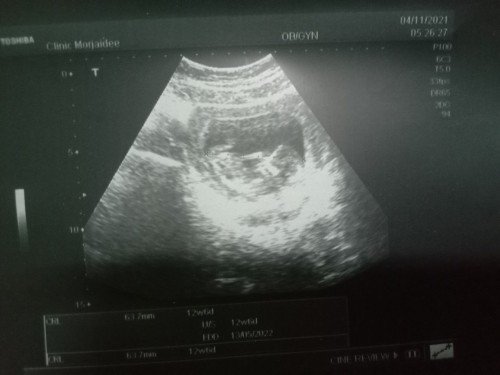

เอาเบบี้มาโชว์กันค่ะ #12+5d

ไปอัลตร้าซาวด์ตอนท้อง12w6วันน้องตัวใหญ่มาก ตอนนี้ท้องได้ประมาณ23w2วันเเล้วค่ะยังไม่รุ้เพศเลย